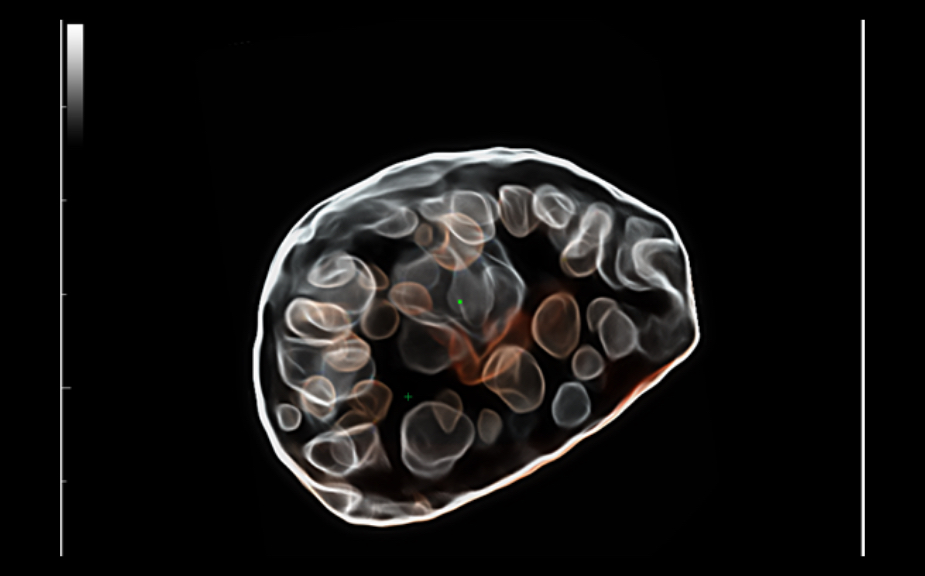

Obrazy kliniczne